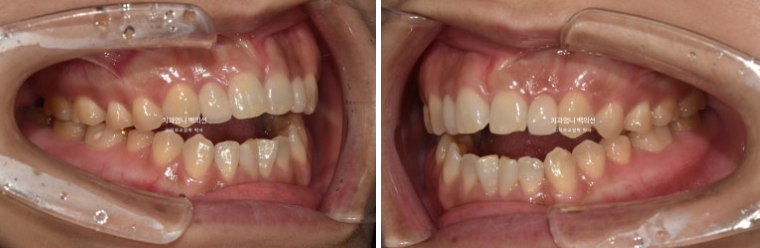

23.10

치료 시작 5개월차, 어금니 함입만으로도 앞니 개방교합이 많이 해소가 되었습니다.

사진에서 보듯이 어금니가 잇몸에 파묻히기 직전까지 함입을 시켰으니 이제 남은 개방교합은 앞니쪽에서 해결을 봐야죠. 이때부터 앞니를 정출시키기 위해 클리피씨 장치를 위아래 모두 부착했습니다.